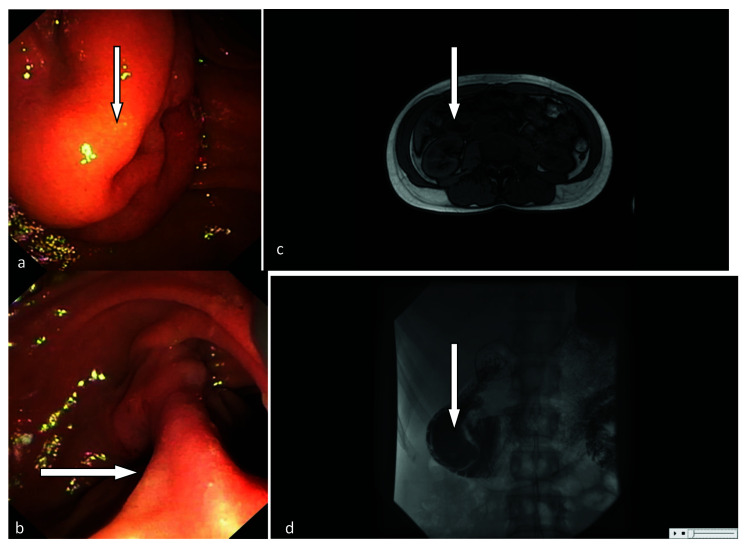

Intraluminal duodenal diverticulum is a rare entity that may cause recurrent pancreatitis. We report a case of a 36-year-old female admitted with etiologically unclear, recurrent pancreatitis. Radiographic study and endoscopy revealed a sac-like structure of the second portion of the duodenum near the minor duodenal papilla. Endoscopic diverticulotomy was successfully performed. No complications were observed and the patient was discharged home a day later. After 62-month follow-up, the patient was active and without symptoms. To our knowledge, this is the first reported case of recurrent pancreatitis caused by intraluminal duodenal diverticulum near the minor duodenal papilla, treated with endoscopic diverticulotomy performed from the apex to the base of the diverticulum.